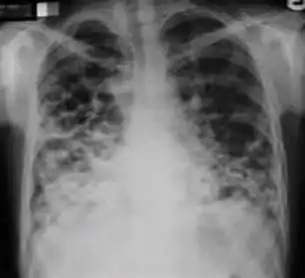

Radiology (X-rays) is used in the diagnosis of tuberculosis. Abnormalities on chest radiographs may be suggestive of, but are never diagnostic of TB, but can be used to rule out pulmonary TB.

In active pulmonary TB, infiltrates or consolidations and/or cavities are often seen in the upper lungs with or without mediastinal or hilar lymphadenopathy.[1] However, lesions may appear anywhere in the lungs. In HIV and other immunosuppressed persons, any abnormality may indicate TB or the chest X-ray may even appear entirely normal.[1]

Old healed tuberculosis usually presents as pulmonary nodules in the hilar area or upper lobes, with or without fibrotic scars and volume loss.[1] Bronchiectasis and pleural scarring may be present.

Nodules and fibrotic scars may contain slowly multiplying tubercle bacilli with the potential for future progression to active tuberculosis.[1] Persons with these findings, if they have a positive tuberculin skin test reaction, should be considered high-priority candidates for treatment of latent infection regardless of age. Conversely, calcified nodular lesions (calcified granuloma) pose a very low risk for future progression to active tuberculosis.

Abnormalities on chest radiographs may be suggestive of, but are never diagnostic of, TB.[1] However, if a person has a positive response to the tuberculin skin test and no symptoms of the disease, chest radiographs can be used to rule out the possibility of pulmonary TB.